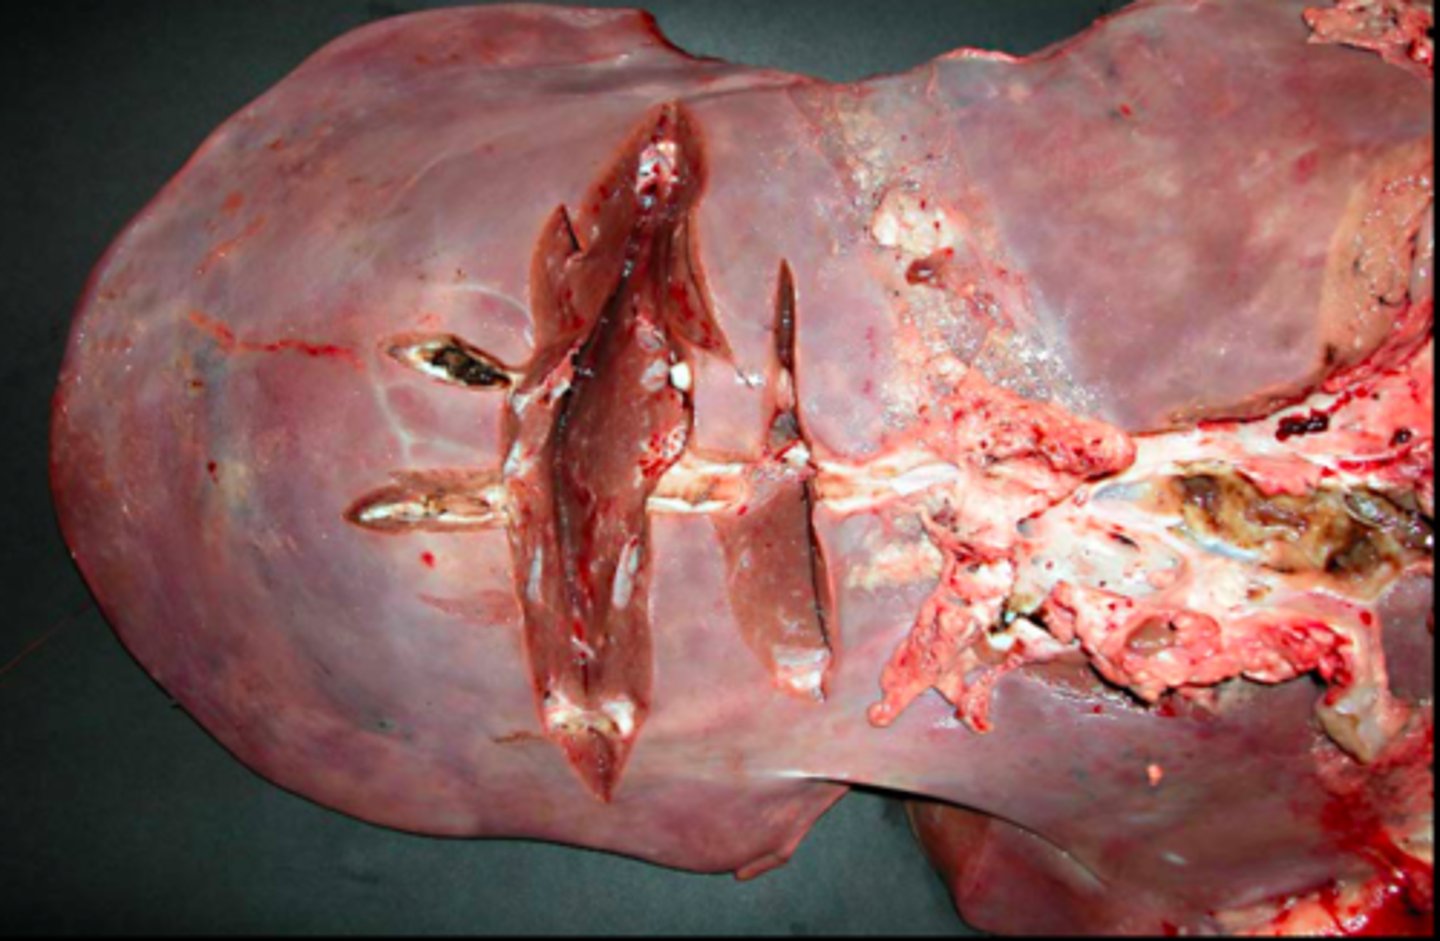

Akut, hæmorrhagisk og nekrotiserende hepatitis.

Ætiologi: infektion med Fasciola heptatica

Lever fra får, hvad er den patoanatomiske diagnose og ætiologien?